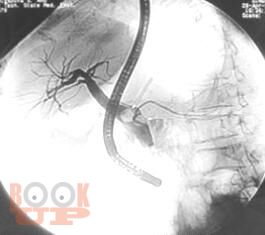

Неотложная хирургия - одно из наиболее актуальных, сложных и ответственных направлений хирургии. Пациенты пожилого и старческого возраста с механической желтухой различной этиологии толстой кишки составляют значительный контингент, госпитализируемый в хирургические стационары по экстренным показаниям. Издание реализовано с учетом опыта сотрудников кафедры и современных представлений о патогенезе, методах эндоскопической диагностики, клинических проявлениях и основных принципах лечения больных синдромом механической желтухи, обусловленной осложнениями патологии гепатопанкреатодуоденальной зоны и желудочно-кишечного тракта. Успех в лечении таких пациентов во многом зависит от своевременности и точности постановки диагноза.